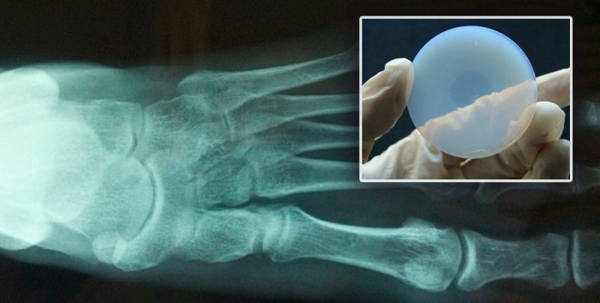

EEUU.,11/10/2016(El Pueblo en Línea)-Viajar a Marte, un reto que la NASA se prepara para conseguir a partir de 2030 y que también persiguen algunas empresas privadas, se convertirá en la haza?a del milenio, pero la gran aventura está plagada de peligros, entre ellos los que supone estar sometido a las altísimas dosis de radiación de partículas provenientes del espacio durante el trayecto. Un estudio publicado en la revista Science en 2013 decía que la exposición acumulada, para un astronauta con billete de ida y vuelta, sin contar la estancia más o menos prolongada en el Planeta rojo, equivale a hacerse 33.000 radiografías. Ahora, investigadores de la Universidad de California Irvine (UCI) se han interesado por lo que supondría esa radiación para el cerebro humano y sus conclusiones elevan aún más la alarma. Los astronautas que viajen a Marte podrían sufrir demencia crónica. Quizás, a su regreso, ni se acordarían del viaje, según ABC.

Según describe en Scientic Reports Charles Limoli, profesor de oncología radiactiva en la Escuela de Medicina de la UCI, la exposición a las partículas cargadas de alta energía -al igual que las que se encuentran en los rayos cósmicos que bombardean a los astronautas durante los vuelos espaciales prolongados- causan importantes da?os cerebrales a largo plazo en roedores, lo que resulta en alteraciones cognitivas y demencia. Limoli ya dio a conocer sus resultados en 2015, pero ahora ha ampliado su estudio, comprobando los efectos con el paso del tiempo.